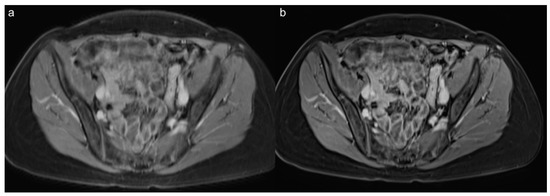

3.3. Qualitative Results of the Precontrast Images

3.4. Qualitative Results of the Postcontrast Images